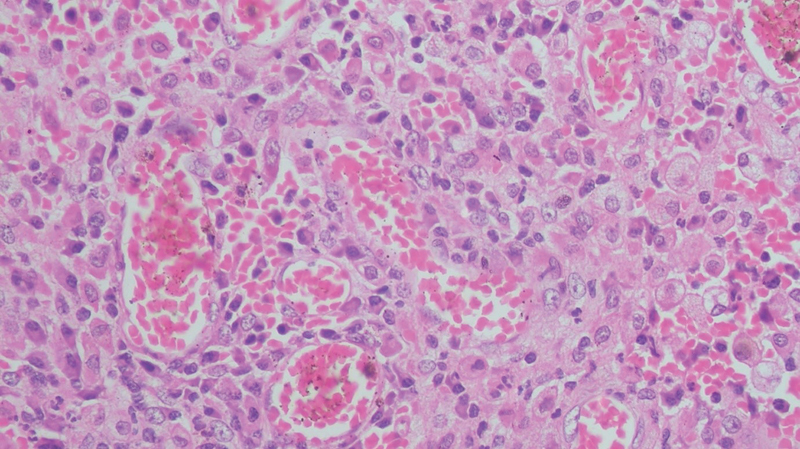

On microscopic examination, the cyst wall was seen to be comprising of fibrocollagenous tissue, infiltrated by sheets of foamy macrophages, lymphocytes, plasma cells, and neutrophils ([Fig. 1], [2], [3]). Proliferating blood vessels were noted. Few areas showed fibrosis with hemosiderin-laden macrophages. Endometrial glands or stroma was not seen. The features like atypia and dysplasia were characteristically absent. The appendix showed normal histomorphology with periappendiceal inflammation. CD68 immunohistochemistry confirmed the presence of foamy histiocytes ([Fig. 4], [5]), while pan-cytokeratin was negative. Diagnosis of xanthogranulomatous oophoritis was made, based on the histomorphological features.

| Fig. 2 The presence of large number of foamy histiocytes admixed with plasma cells, lymphocytes, and occasional neutrophils, is seen, which is pathognomonic feature of xanthogranulomatous oophoritis (hematoxylin and eosin staining; magnification 100x).

The gross appearance of the specimens may show cystic degeneration, foci of necrosis, and hemorrhage, in grossly enlarged ovary. The microscopic examination shows the presence of foamy histiocytes, along with a mixture of inflammatory cells like lymphocytes, plasma cells, and occasional neutrophils.[21] Foamy histiocytes, the so-called “xanthoma cells,” are histiocytes with abundant lipid-laden cytoplasm having a vacuolated appearance. These impart the yellowish color to the specimen, when seen on the gross examination. There is no cellular atypia, abnormal mitoses, or any other microscopic feature suggestive of malignancy.